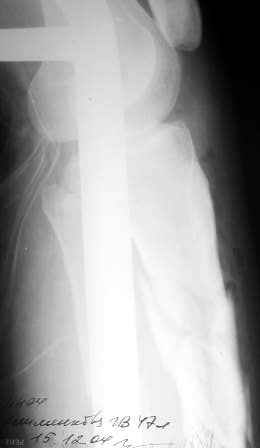

Больная поступила 11 12 2004 с открытым оскольчатым переломом в/3 обеих костей правой голени со смещением после автодорожной аварии. (1Б по Каплану, тип 2-классификация Gustilo-Anderson).

Наложено скелетное вытяжение . обработана рана, наложены швы, заживление идет благоприятно. На контрольных рентгенограммах стояние отломков несколько улучшилось. Рис 1,2 Обдумываем в коллективе несколько вариантов возможного лечения:

Рентгенограмма при поступлении. Думаю на ней видно распространение линии перелома вниз